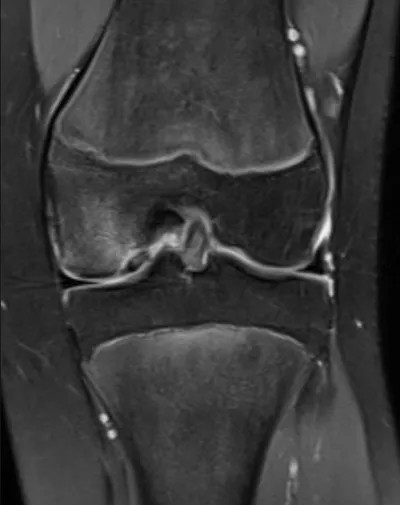

Cartilage Radiology Images

Browse 4 medical images tagged with cartilage. This collection includes various imaging modalities for medical education and reference.

- This collection contains 4 radiology images related to cartilage, including various imaging modalities such as X-rays, MRIs, CT scans, and ultrasound images commonly used in medical diagnosis and education.